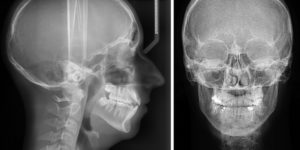

Как правило, рентген проводится в двух проекциях:

- прямой (фронтальной);

- боковой (сагиттальной).

Это объясняется тем, что рентгенограмма — это плоское изображение трехмерного объекта. Чаще всего достаточно двух проекций, чтобы установить локализацию патологических изменений.

Однако бывают ситуации, когда необходимо более точное определение места, в котором обнаружена патология, а также более детальное изучение степени ее развития. Тогда для достижения более качественного результата рентген проводят и в других проекциях, а именно посредством:

- Правой и левой боковой проекции.

- Переднезадней, которая известна в медицинских кругах как проекция Тауна.

- Заднепередней, так называемая проекция Колдуэлла.

- Аксиональной. В данном случае рентген проводится вдоль оси тела.

Снимки, получаемые в перечисленных проекциях, являются максимально информативными, и дают возможность рассмотреть костные или мозговые патологии в мельчайших подробностях.